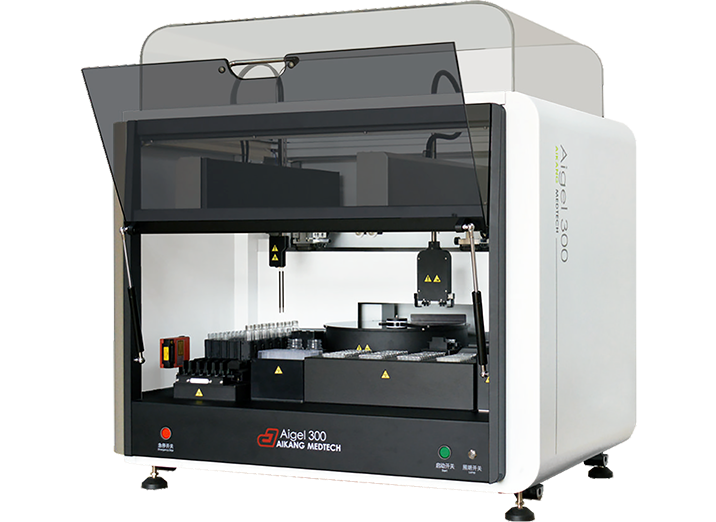

Aigel全自动血型分析仪采用微柱凝胶卡法,操作简便,灵敏度高,可检出低含量抗原抗体,结果清晰可靠、便于保存,并满足多种数据管理的要求,适用于各类大中小医院、血站、疾控中心等单位的ABO血型正反定型自动化检测、Rh(D)和不规则抗体筛选、交叉配血等。

适用于ABO血型正反定型自动化检测、Rh(D)和不规则抗体筛选、交叉配血等

结果准确,操作简便,灵敏度高,可检出低含量抗原抗体

批量输入病人信息,样本测试批量处理;各模块协同工作,效率更高

CCD数码成像,原始图像结果可永久保存,便于查询和追溯

支持多种条码自动扫描识别,急诊样本优先处理,微柱凝胶卡灵活放置,上机自动检测试剂液量

支持与医院、血站双向LIS通讯,测试信息手动/自动获取、发送,支持异常信息自动识别、提示

Aigel系列目前拥有多种型号可供选择,满足不同的临床需求